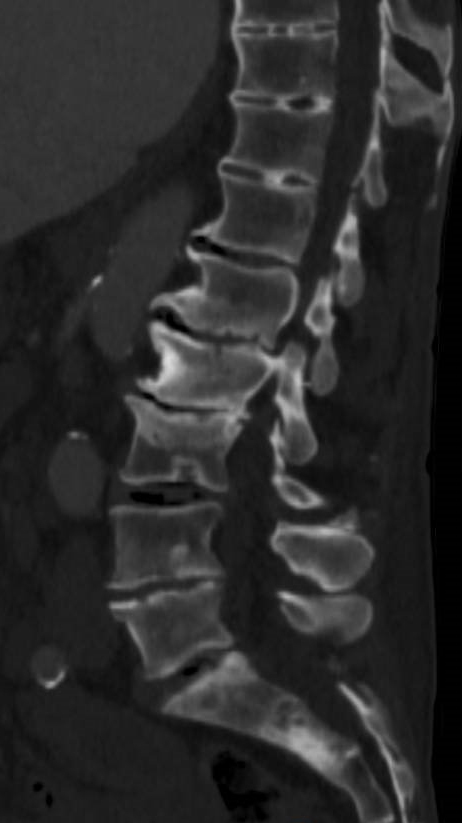

Le patient bénéficie d’une imagerie par scanner du rachis.

Question 4 - En interprétant ces images, vous notez (une ou plusieurs réponses correctes) :

Non visible ici, en revanche il existe des hernies intraspongieuses qui ont une origine mécanique.

Notamment au niveau sacré et L2.

Vide discal (pincement), géodes, ostéophytes et ostéocondensation sous chondrale.

Image lytique en miroir non visible ici, en revanche il existe des hernies intraspongieuses qui ont une origine mécanique.

Les métastases osseuses peuvent être ostéolytiques et/ou ostéocondensantes (caractéristique assez spécifique, avec possible vertèbre ivoire).

Vous réalisez une TDM et une IRM rachidienne qui retrouvent des lésions osseuses ostéocondensantes du rachis lombaire et sacrées sans retentissement neurologique. Le PSA sérique total est à 700 ng/mL. Vous suspectez un cancer prostatique métastatique.